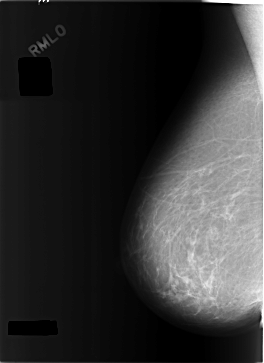

C_0301_1.RIGHT_MLO

RIGHT_MLO LINES 5800 PIXELS_PER_LINE 4216 BITS_PER_PIXEL 12 RESOLUTION 50 NON_OVERLAY